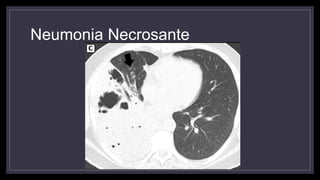

Neumonía Necrosante

• Se da en pacientes inmunodeprimidos y enfermos crónicos

• Asociada a Estafilococo Aureus (sobre todo meticilino resistentes y

positivos para Panton Valentine Leukocidin), Klebsiela, Anaerobios.

• Gran necrosis de tejido pulmonar

• Inicialmente se observan áreas radiolúcidas dentro de una

consolidación que luego confluyen para formar una cavidad que

Neumonia Necrosante